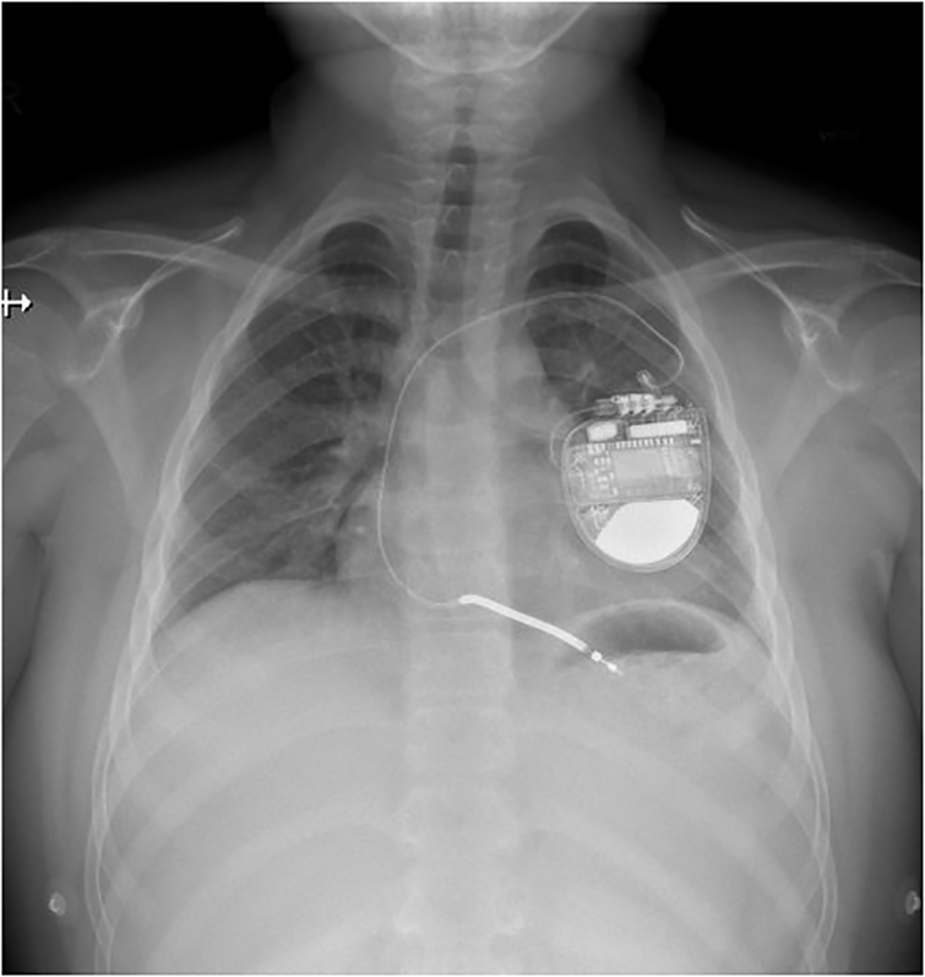

Figure 2

Transvenous implantable cardioverter-defibrillator implanted in patient with GS.

10-year-old boy (refugee from Ukraine) collapsed in the tram in the city of Prague. Lay cardiopulmonary resuscitation was initiated with subsequent arrival of healthcare professionals. Sinus rhythm was restored within a few minutes by external defibrillation of the documented ventricular fibrillation (Figure 1). The patient was intubated, sedated and transported to the pediatric anesthesiologic ward, with no major physical findings except for pathologic lung auscultation—crackling and wheezing over the right lung caused by aspiration pneumonia, managed by parenteral antibiotic therapy (amoxycilin/clavulanate). On admission, the patient was stable under sedation, intubated with no reaction to examination (Glasgow coma scale 3). Therapeutic hypothermia was slowly withdrawn after 24 h. Electrocardiogram (ECG) showed normal sinus rhythm with age-appropriate heart rate and normal repolarization, with QTc of 422 ms (including normal QTc during 24 h ECG monitoring) and normal echocardiography findings. The initial laboratory results were as follows: serum sodium 133 mmol/L, potassium 2.5 mmol/L, chloride 96 mmol/L, calcium 2.25 mmol/L, magnesium 0.78 mmol/L, urea 7.4 mmol/L, creatinine 66 µmol/L, bicarbonate 22.9 mmol/L. Parenteral electrolyte supplementation was started, high potassium chloride (KCl) supplementation 8–10 mmol/kg/day was required to maintain potassium in the low normal range, magnesium was supplemented later when serum levels were decreased. The patient was extubated on the second day with normal neurologic examination and transported to Children's Heart Centre on the 4th day of hospitalization. Oral celecoxib (3.5 mg/kg/day) was started after 7 days to reduce the extensive oral and parenteral KCl supplementation. Single-chamber (transvenous lead) implantable cardioverter-defibrillator (ICD) was implanted for secondary prevention of sudden cardiac death (Figure 2). The patient was discharged from the hospital after 28 days. He has been followed up regularly by a pediatric nephrologist and cardiologist, with satisfactory potassium and magnesium serum levels in the long term, >3 mmol/L and >0.6 mmol/L, respectively. Since the device implantation, the remote ICD monitoring recorded several episodes of asymptomatic non-sustained polymorphic ventricular tachycardia, with no appropriate therapies needed so far. Molecular genetic examination performed by next-generation sequencing (Clinical Exome Solution v3 by Sophia Genetics, Switzerland) revealed 2 pathogenic (class 5 according to ACMG/AMP guidelines) variants in SLC12A3 gene (NM_001126108) c.2633 + 1G>A and c.2221G>A (p.Gly741Arg) confirming the diagnosis of GS. Subsequent segregation analysis revealed 2 pathogenic (class 5 according to ACMG/AMP guidelines) variants in SLC12A3 gene (NM_001126108) paternally inherited c.2633 + 1G>A and maternally inherited c.2221G>A (p.Gly741Arg).